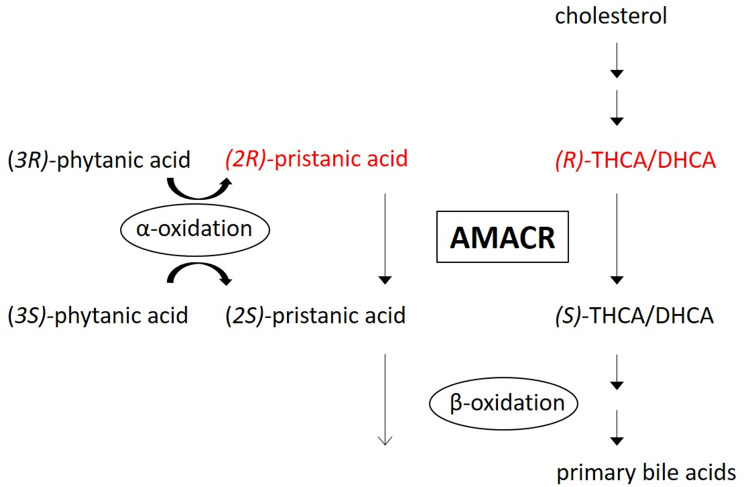

Alpha-methylacyl-CoA racemase (AMACR) deficiency is an autosomal recessive peroxisomal disorder caused by pathogenetic variants in the AMACR gene that was first described in 2000 [ref. 1]. AMACR is responsible for the conversion of fatty acids with a methyl group in the (R)-configuration, including the branched-chain fatty acid pristanic acid and the C27-bile acid intermediates (R)- trihydroxycholestenoic acid (THCA) and (R)-dihydroxycholestenoic acid (DHCA), to the corresponding (S)-isomer. The (S)-isomers can be processed by peroxisomal β-oxidation. In the case of AMACR deficiency, bile acid intermediates (R)-DHCA and (R)-THCA and pristanic acid accumulate [ref. 1, ref. 2] (Fig. 1). C27-bile acid intermediates are proven to be toxic, are associated with liver disease in multiple peroxisomal disorders, and are able to cross the blood-brain barrier with evidence of accumulation in brain in other peroxisome deficiency disorders with C27-bile acid intermediates accumulation [ref. 3, ref. 4]. C27-bile acid intermediates are thought to be less capable than the primary C24-bile acids in forming mixed micelles in the small intestinal lumen, leading to malabsorption of fat and thereby of fat-soluble vitamins [ref. 5]. The diagnosis can be established by measuring the above mentioned metabolites in plasma, demonstration of C27– bile acid intermediates in urine, enzyme activity analysis in skin fibroblasts and mutation analysis of the AMACR gene (for review on the diagnosis of peroxisomal disorders and distinction between AMACR deficiency and other peroxisomal disorders see Klouwer et al. [ref. 6]).